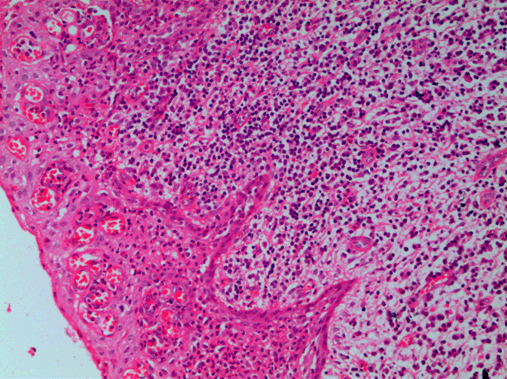

Microscopic examination revealed a hyperplastic non-keratinized stratified squamous epithelium of varying thickness (Figure 3). Epithelium exhibited proliferation in an arcading pattern. An intense inflammatory cell infiltrate was observed in the adjacent fibrovascular connective tissue capsule (Figure 4). The connective tissue was moderately collagenous with diffuse dense chronic inflammatory cells, predominantly lymphocytes and plasma cells. Numerous endothelium lined blood vessels, extravasated RBCs, calcifications and trabeculae of bone were also seen in the connective tissue. The findings were compatible with the diagnosis of inflammatory paradental cyst.

Figure 4: Epithelium exhibiting proliferation with dense inflammatory infiltrate in the adjacent connective tissue (H&E stain, x400).